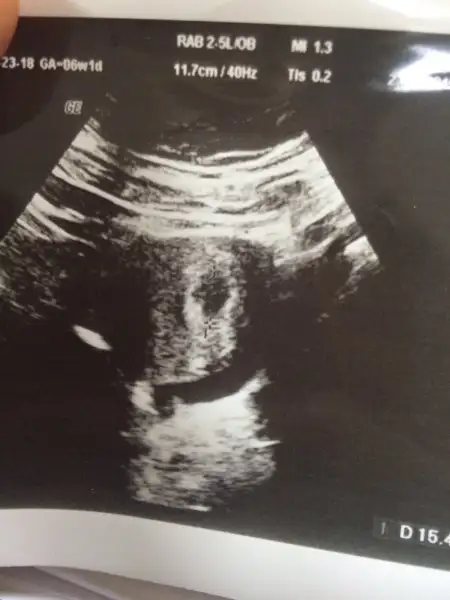

KIZLAR BANADA TAHMİNDE BULUNABİLİRMİSİNİZ 10 HAFTALIK HAMİLEYİM DÜN CEKİLEN BEBEĞİMİN GÖRÜNTÜSÜ

Bu arkadasimin ultrason fotosu:)Ramzi teorisine göre ( bilimsel bir araştırma sonucuymuş ve %85 doğruluğu varmış). İlk 6-8 haftalık ultrason görüntüsüne göre bebeğin kesenin içersinde soldan ya da sağdan girişine göre cinsiyet tahmini yapılıyor. Bilimsel olunca tecrübeli annelerimiz yada anne adaylarımızdan yardım istiyoruz. Doğruluğu var mı öğrenmek adına :) Bizleri aydınlatırsanız çok seviniriz. bu teorieye göre;

Bu arkadasimin ultrason fotosu:)

Sizce kiz mi erkek mi ?